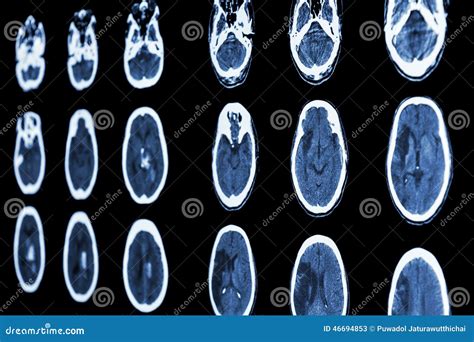

The Role of CT Scans in Diagnosing Ischemic Stroke

Computed Tomography (CT) scans are essential in the diagnosis of ischemic stroke. An Ischemic Stroke CT scan can quickly and accurately detect the presence of a stroke, differentiate it from other conditions, and guide treatment decisions. The scan uses X-rays to create detailed images of the brain, which can reveal:

• Blood clots: The presence and location of blood clots in the brain.

• Brain tissue damage: The extent of damage to brain tissue caused by the stroke.

• Hemorrhage: Whether the stroke is ischemic or hemorrhagic, which is crucial for determining the appropriate treatment.

CT scans are particularly valuable in the acute phase of a stroke, where time is of the essence. They can be performed quickly and are widely available in most hospitals, making them a first-line diagnostic tool.